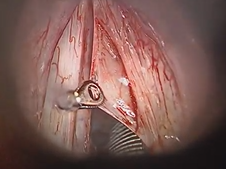

Uvulopalatopharyngoplasty (UPPP)- Lateral Expansion Pharyngoplasty Variant with Uvulopalatal Flap

Retrosigmoid Approach for Resection of Vestibular Schwannoma with Hearing Preservation